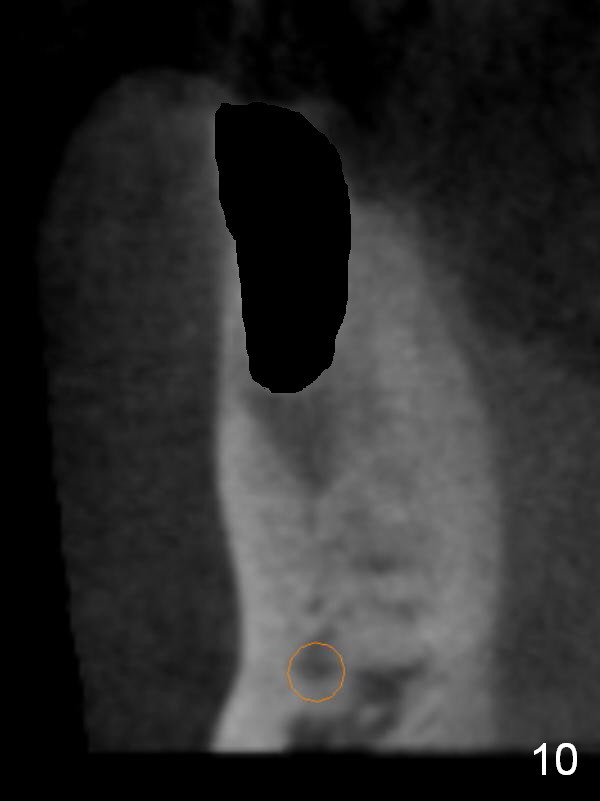

CT sagittal section shows that it is possible to place 4.5x20 mm implant (Fig.6). Axial (Fig.7) and coronal (Fig.9) sections show that the lingual (L) plate is much thicker than the buccal (B) one. To prevent the implant being buccally deviated, a Lindermann bur is used after extraction (black area in Fig.8,10) to remove ~ 1mm bone from the lingual plate (red area in Fig.8,11). A 2 mm pilot drill is placed as lingual as possible (green in Fig.8,11). If the implant (Fig.12) starts to deviate buccally while being placed, remove it from the osteotomy and remove more bone from the lingual plate. Place the implant again and monitor the trajectory tightly.